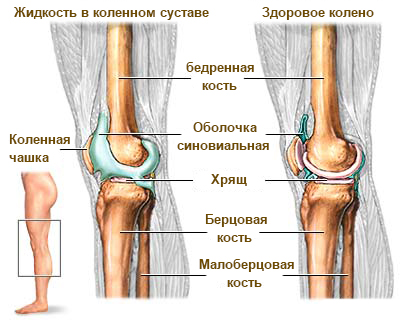

Синовиальная ткань и выделяемая ею жидкость – играют важную роль в выполнении своих функций суставом. Синтезируемая жидкость содержит в себе питательные вещества, углеводы и белки. Она выполняет амортизирующую и питательную функции. Благодаря синовиальной жидкости происходит питание хрящевых тканей в суставах.

При развитии синовита эта жидкость выделяется в большем количестве. Происходят изменения в ее составе: концентрация питательных веществ снижается, а следовательно, понижается и качество жидкости. В той, что вырабатывается во время болезни, могут появляться примеси кровяных телец, гнойных образований и инфекции. Получаемая жидкость в медицине называется выпотом.

Синовитом называют воспалительный процесс в синовиальной ткани находящейся в суставе, вследствие которого происходит чрезмерное выделение синовиальной жидкости. Этот недуг не протекает обособленно и является следствием других болезней. Наиболее часто встречается синовит колена, хотя может развиваться и в других частях тела. В международной номенклатуре он имеет код по МКБ 10. Далее рассмотрим признаки и как лечить синовит коленного сустава различными методами.